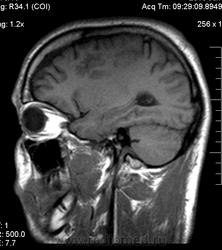

Мужчина 32 лет. Из анамнеза: перинатальное повреждение ЦНС, ДЦП, дизартрия, правосторонний верхний монопарез. С 16 лет приступы эпилепсии.

Аплазия прозрачной перегородки. Шизэнцефалия с открытыми краями в лобно-теменной области слева. Шизэнцефалия с закрытыми краями в лобной области справа? Утолщение коры по контуру расщелин и в области глазничной извилины правой лобной доли. Микрогирия? Гиперостоз костей свода черепа. Уважаемые коллеги, возможно я ошибаюсь, или есть еще аномалия?

На мой взгляд, полимикрогирия двусторонняя (конвекситальные отделы дорзальных отделов лобных долей и частично теменных, а также в базальном отделе полюса правой лобной доли) + закрытая шизенцефалия левой лобно-теменной области. Аплазия прозрачной перегородки (как признаки лобарной голопрозенцефалии).